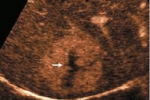

L'ecografia con mdc e' di ausilio nella DD  delle lesioni focali epatiche indeterminate alla MSTC

L'ecografia con mezzo di contrasto puo' essere di ausilio nella diagnosi differenziale delle lesioni focali epatiche subcentimetriche dall'aspetto dubbio alla TC multistrato Indeterminate, subcentimetric focal liver lesions in cancer patients:... ...

L'ecocontrastografia può caratterizzare le lesioni focali  epatiche senza dover ricorrere a TC o RM

Può l'ecocontrastografia caratterizzare lesioni focali epatiche e differenziale tra benigne e maligne evitando il ricorso ad altre tecniche d'imaging? Can contrast-enhanced ultrasonography characterize focal liver lesions and differentiate between... ...